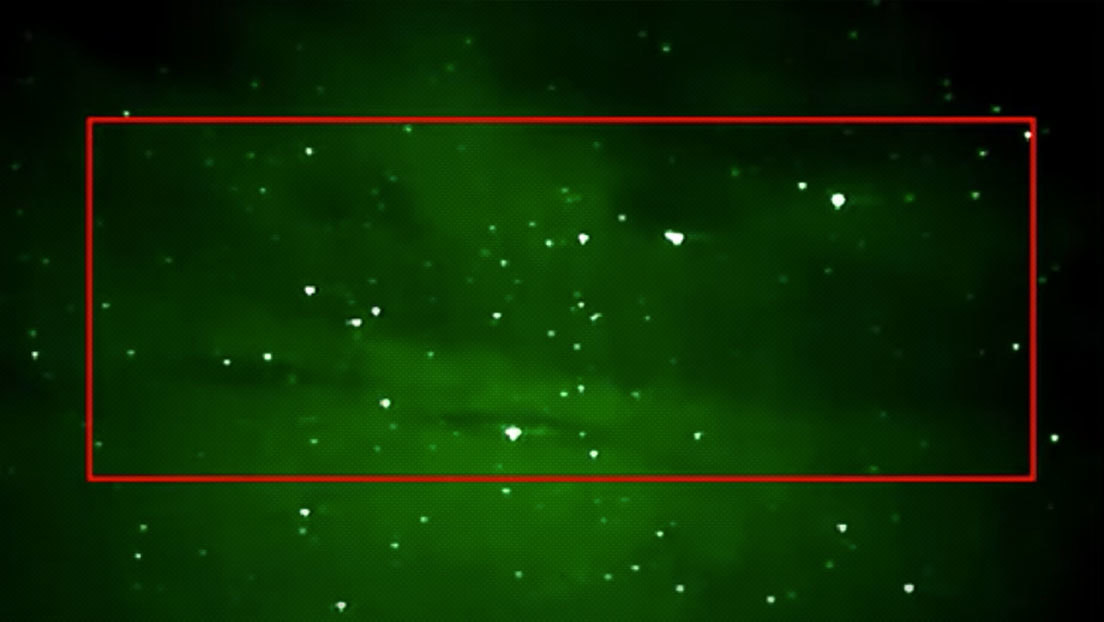

Para despejar estas dudas, los autores del estudio ahora buscaron evidencia de secuencias virales dentro del genoma humano con ayuda de tres técnicas diferentes de secuenciación de ADN. Y en cada oportunidad hallaron fragmentos de material genético del SARS-CoV-2 insertados en las células infectadas.

Los investigadores observaron que estas secuencias presentaban huellas genéticas de transposones —o genes saltarines—, un tipo de secuencia de ADN capaz de desprenderse de una región del genoma y reinsertarse en otra.

Los científicos sospechan que una clase particular de estas secuencias, conocida como retrotransposones LINE1 y que compone el 17 % del genoma humano, podría facilitarle al coronavirus el acceso a nuestro ADN.